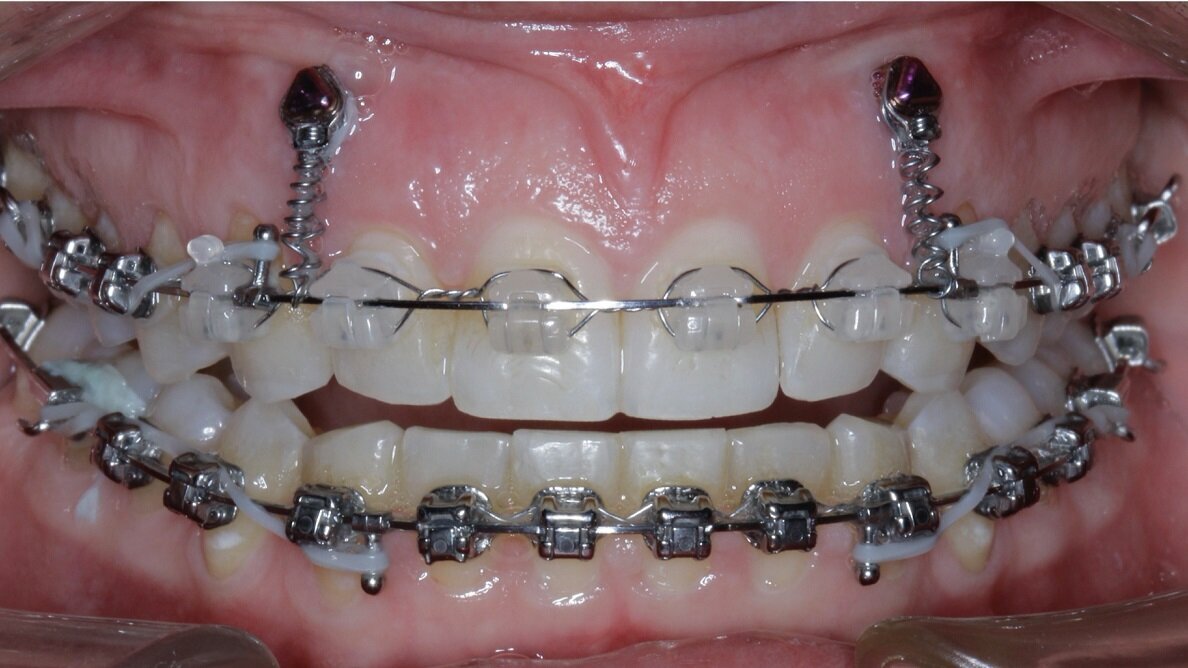

A case is considered an absolute gummy smile when there is absolute maxillary excess (Figs. 24 & 25, beginning of treatment). These cases combine the previously described methods, using a total of four TADs. Two anterior TADs are placed between tooth #12 and #13 and between tooth #22 and #23, two posterior TADs are placed between tooth #16 and #15 and between tooth #25 and #26 or between tooth #15 and #14 and between tooth #24 and #25, and bite turbos are placed on teeth #36 and #46 with Triad Gel (Fig. 26).

In some cases, intrusion may occur asymmetrically (one side faster than another, or the anterior faster than the posterior). For these occurrences, when one area has been completed with intrusion, the TAD is tied to the wire and intrusion continues in the others until all intrusion has been completed. A gingivectomy and hard-tissue contouring are completed (Figs. 27–29, end of treatment).